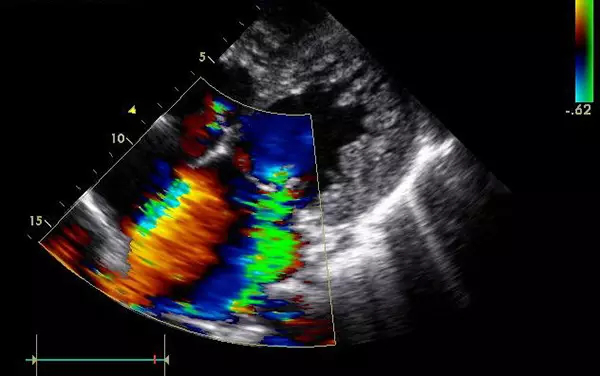

B超

B超的原理是用超聲波穿透人體,當(dāng)聲波遇到人體組織時(shí)會(huì)產(chǎn)生反射波,通過計(jì)算反射波成像。

優(yōu)點(diǎn):多方向觀察,實(shí)時(shí)成像。

缺點(diǎn):超聲受氣體干擾很大,對(duì)于腸道等含氣較多的器官,超聲診斷準(zhǔn)確率會(huì)降低,所以一般腸道檢查使用腸鏡。

4、腹部盆腔——除腸道外,一般超聲都能查

眾所周知的應(yīng)該就是懷孕期間胎兒的相關(guān)檢查,用B超都能看的很清楚;另外,甲狀腺等淺表器官,以及肝臟、脾臟、胰腺、腎臟、盆腔等實(shí)質(zhì)臟器,B超診斷準(zhǔn)確率都較高。

5、心臟——排除冠心病用CT,看心功能用超聲